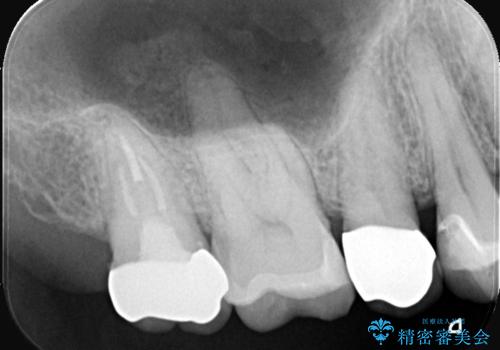

- お口の中にある銀歯を全てなくして、白く健康的な状態にしたい」という主訴でご来院されました。長年使用してきた複数の銀歯は、経年劣化により適合が悪くなっており、一部では内部で二次カリエス(虫歯の再発)も認められました。

銀歯の除去と精密な再治療: 古い銀歯を一つひとつ丁寧に取り外し、内部の虫歯を徹底的に除去。神経を保護するための処置を行った上で、適合性を極限まで高めるために精密な型取りを行いました。

オールセラミックによる修復: 天然歯のような光の透過性と硬さを持つオールセラミックを使用しました。奥歯であっても、患者様固有の歯の色調や咬み合わせの溝を忠実に再現した修復物を装着。金属を一切使用しないことで、金属アレルギーのリスクを排除し、歯肉の色が黒ずむ心配もなくなりました。

【治療の結果】 全ての銀歯が白くなったことで、お口の中がパッと明るくなりました。見た目の美しさだけでなく、表面が滑らかなセラミックはプラークが付着しにくいため、将来的な虫歯や歯周病の予防効果も高まった健康的な口腔環境が実現しました。